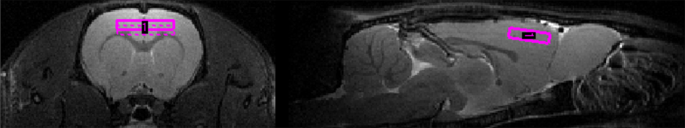

Experiments were performed on a 7.0 Tesla Animal Biospec MR Scanner (Bruker, Ettlingen, Germany). Two coils were used: a cylindrical transmitter coil with a 72 mm internal diameter and a surface coil, which was placed on the scalp of each animal for signal reception. Gradient echo acquisition was first carried out to confirm the placement of the animal in the apparatus. T2-weighted anatomical sequences were then carried out in the axial and sagittal planes to position the MRS acquisition voxel (1 * 6 * 4 mm3) in the prefrontal cortex22 (Fig. 4). The acquisition parameters were as follows: TR/TE = 2500/33 ms, squared field of view = 4 cm, encoded by a squared matrix of 256 and 16 slices of 0.5 mm.